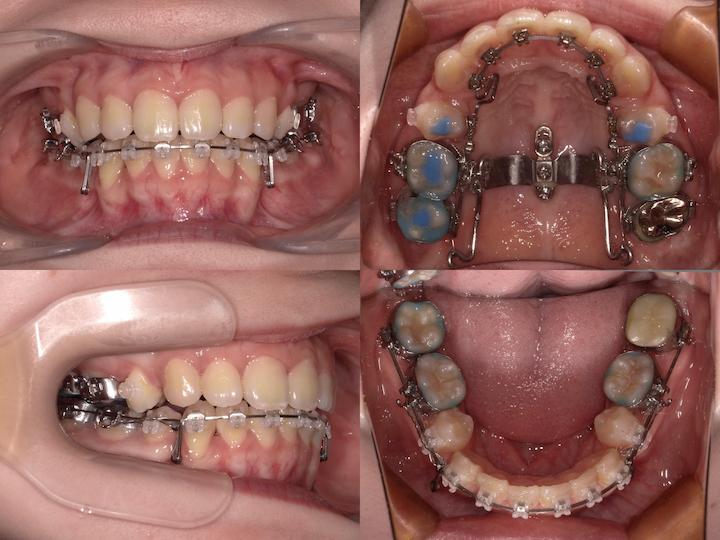

治療方法

初診時年齢33歳5ヶ月の患者様です。口の閉じ辛さと歯の重なりを主訴にご来院されました。

上下左右4番を抜歯してアンカースクリューで上顎6番を遠心移動しながら前歯を後方に牽引しました。

さらに上顎大臼歯を圧下(上方向に移動)して下顎骨の前上方への回転を促しました。